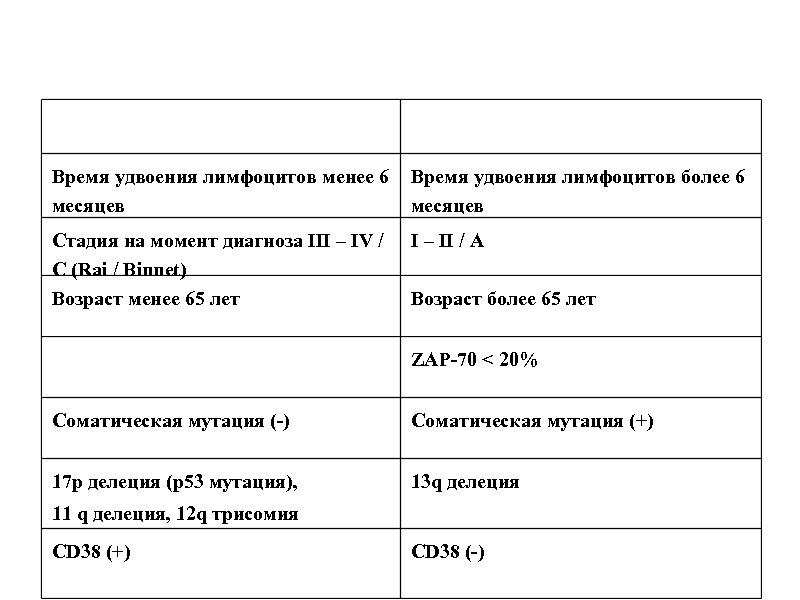

Время удвоения лимфоцитов менее 6 месяцев Время удвоения лимфоцитов более 6 месяцев Стадия на момент диагноза III – IV / C (Rai / Binnet) Возраст менее 65 лет I – II / A Возраст более 65 лет ZAP-70 < 20% Соматическая мутация (-) Соматическая мутация (+) 17 p делеция (p 53 мутация), 13 q делеция 11 q делеция, 12 q трисомия CD 38 (+) CD 38 (-)